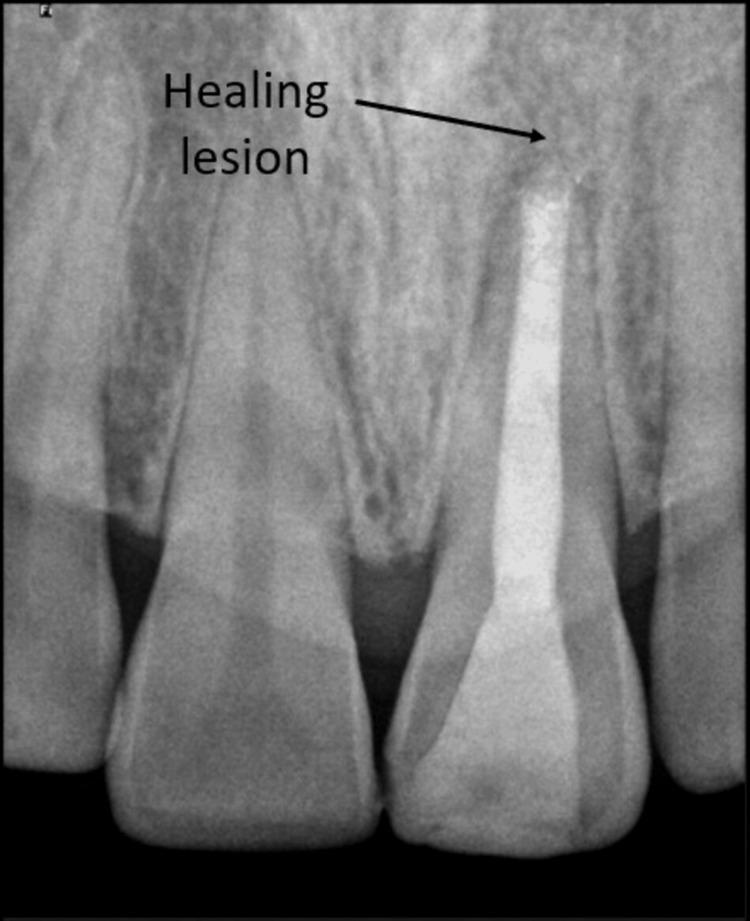

Apexification is a crucial procedure for achieving apical healing in non-vital teeth with open apices. Traditionally, calcium hydroxide has been used for this purpose, but it has significant drawbacks, including prolonged treatment duration, increased risk of root fracture, and the potential for porous barrier formation. Mineral trioxide aggregate (MTA) has emerged as a superior alternative due to its biocompatibility, faster setting time, and better sealing properties. However, MTA extrusion into periradicular tissues can cause persistent discomfort. The use of an internal matrix such as platelet-rich fibrin (PRF) can help contain MTA within the root canal, enhancing treatment outcomes. A 35-year-old female presented with dull, aching pain in tooth 21, a history of trauma 10 years prior, and incomplete root canal therapy 2 years ago. Diagnosis revealed an open apex with chronic apical periodontitis and pulpal necrosis. Initial management involved canal disinfection with sodium hypochlorite (NaOCl) and calcium hydroxide as intracanal medication. One week later, the patient returned asymptomatic. PRF was prepared from the patient's blood and used as an internal matrix. Mineral trioxide aggregate was then placed against the PRF membrane to form an apical stop. The canal was subsequently obturated with thermoplasticized gutta-percha and restored with composite resin. The use of PRF and MTA provided effective apical sealing, preventing material extrusion and promoting tissue healing. The PRF matrix facilitated the controlled placement of MTA, minimizing complications and enhancing periapical healing. The combination of PRF as an internal matrix and MTA for apical barrier formation represents a promising approach for managing non-vital teeth with open apices. This technique ensures better control over material placement, reduces treatment time, and improves the overall success of endodontic therapy. The aim of this case report is to describe the endodontic management of a non-vital permanent tooth with an open apex and chronic apical periodontitis using a single-step apical barrier technique with MTA and PRF as an internal matrix.

根尖诱导成形术是使根尖孔开放的无髓牙实现根尖愈合的关键步骤。传统上,氢氧化钙一直用于此目的,但它有显著缺点,包括治疗时间延长、根折风险增加以及形成多孔屏障的可能性。由于其生物相容性、更快的凝固时间和更好的封闭性能,矿物三氧化物凝聚体(MTA)已成为一种更优的替代材料。然而,MTA挤出到根尖周组织中会导致持续不适。使用富含血小板纤维蛋白(PRF)等内部基质有助于将MTA限制在根管内,提高治疗效果。一名35岁女性,主诉21号牙钝痛、隐痛,10年前有外伤史,2年前根管治疗未完成。诊断显示根尖孔开放伴慢性根尖周炎和牙髓坏死。初始治疗包括用次氯酸钠(NaOCl)和氢氧化钙进行根管消毒并作为根管内用药。一周后,患者复诊时无症状。从患者血液中制备PRF并用作内部基质。然后将矿物三氧化物凝聚体放置在PRF膜上以形成根尖屏障。随后用热塑牙胶充填根管并用复合树脂修复。PRF和MTA的使用提供了有效的根尖封闭,防止材料挤出并促进组织愈合。PRF基质有助于MTA的可控放置,将并发症降至最低并促进根尖周愈合。PRF作为内部基质与MTA联合用于根尖屏障形成是处理根尖孔开放的无髓牙的一种有前景的方法。该技术可更好地控制材料放置,缩短治疗时间并提高根管治疗的总体成功率。本病例报告的目的是描述使用以MTA和PRF作为内部基质的单步根尖屏障技术对一颗根尖孔开放且患有慢性根尖周炎的无髓恒牙进行根管治疗的情况。